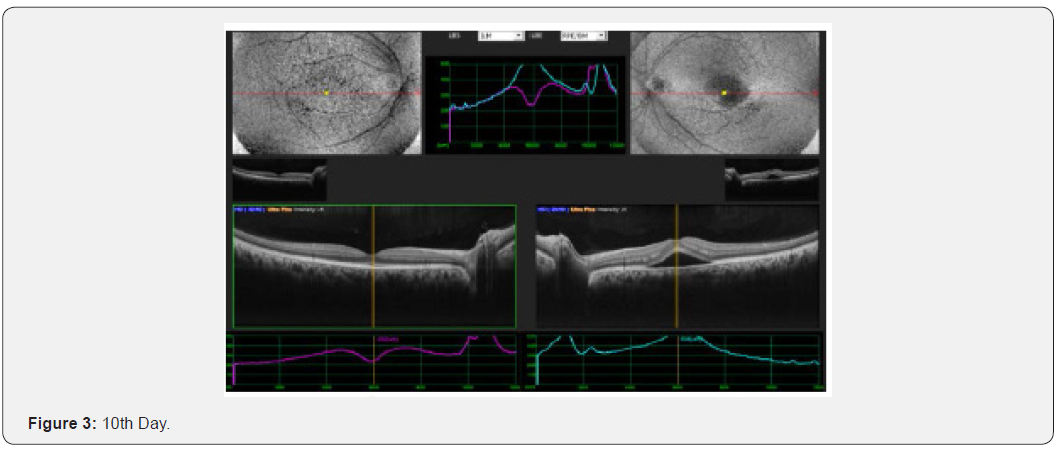

Results: This interventional study includes 21 patients who were diagnosed as acute CSC and followed from the day of presentation to 30th day. All 21 patients were undergoing intervention by using topical bromfenac eye drop, one drop twice daily for 30 days. Macular thickness and visual acuity recorded from the day of presentation up to 30th day. (Table 6) shows all changes before and after treatment and (Figure 1-4) shows early resolution of sub-macular fluid in one of these patients treated with topical bromfenac eye drops (one drop twice daily). In group 1 the macular thickness (CFT) improve from 422-485 microns at onset to 317-382 microns on 5th day becomes 246-295 on 10th day while 210-226 on 30th day. Vision improved from 0.4 to 0.7 at 5th day, improved to 0.8 on 10th day and remained same on 30th day. In group 2 the CFT reduced from 535-565 microns to 401-440 microns on 5th day becomes 318310 on 10th day and on 30th day it was 221-232 microns with improvement in visual acuity which was 0.2 at onset to 0.6 at 5th day, 0.7 at 10th day and improved to 0.8 on 30th day. In group 3 the CFT reduced from 657-722 microns to 456-469 microns on 5th day, 259-366 microns on 10th day while 206-227 microns on 30th day. Visual acuity improved from CF at onset to 0.4 on 5th day, 0.6 on 10th day and improved to 0.7 on 30th day. Conclusion: This, simple, safe, affordable and easily available treatment modality in all parts of the world with early rehabilitation of acute CSC patients.

This interventional retrospective as well as prospective study includes 21 patients who were diagnosed as acute CSC and followed from the day of presentation to 30th day. All 21 patients were undergoing intervention by using topical bromfenac eye drop, one drop twice daily for 30 days. Macular thickness and visual acuity recorded from the day of presentation up to 30th day. (Table 6) shows all changes before and after treatment and (Figure 1-8) shows early resolution of sub-macular fluid in one of these patients treated with topical bromfenac eye drops (one drop twice daily). In group 1 the macular thickness (CFT) improve from 422-485 microns at onset to 317-382 microns on 5th day becomes 246-295 on 10th day while 210-226 on 30th day. Vision improved from 0.4 to 0.7 at 5th day, improved to 0.8 on 10th day and remained same on 30th day. In group 2 the CFT reduced from 535-565 microns to 401-440 microns on 5th day becomes 318-310 on 10th day and on 30th day it was 221-232 microns with improvement in visual acuity which was 0.2 at onset to 0.6 at 5th day, 0.7 at 10th day and improved to 0.8 on 30th day. In group 3 the CFT reduced from 657-722 microns to 456-469 microns on 5th day, 259-366 microns on 10th day while 206-227 microns on 30th day. Visual acuity improved from CF at onset to 0.4 on 5th day, 0.6 on 10th day and improved to 0.7 on 30th day.